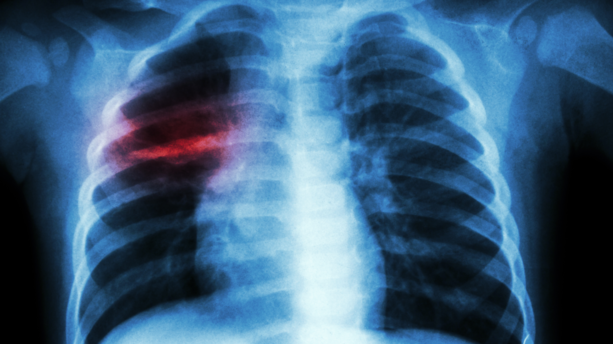

Le 24 mars, En prélude à la Journée mondiale de lutte contre la tuberculose prévue le 24 mars, le coordonnateur du Programme national de lutte contre la tuberculose (PNT), Fodé Danfakha, a fait le point sur la situation de la maladie au Sénégal. Selon ses déclarations, l’année 2024 a enregistré un total de 16 595 cas de tuberculose, toutes formes confondues. Parmi ces cas, une prédominance masculine est à noter, avec 11 181 hommes contre 5 414 femmes touchés par la maladie.

Fodé Danfakha a souligné que la tuberculose touche principalement les adultes jeunes. Cette tranche d’âge représente une grande partie de la population active. Ce qui soulève des préoccupations au-delà des enjeux de santé publique. "Cela va avoir un impact socio-économique sur la vie de ces populations. Ce sont des gens qui sont en activité. Cette maladie va impacter leur vie ainsi que leur travail", a-t-il déclaré, soulignant l'importance de la prévention et de la prise en charge rapide de la maladie.

La tuberculose demeure un problème majeur de santé publique au Sénégal. Et cette situation met en lumière les défis à relever pour mieux lutter contre la propagation de cette maladie, en particulier chez les jeunes adultes. Selon Dr Danfakha, l'impact de la tuberculose ne se limite pas à la santé des individus, mais se répercute également sur l'économie. Car les malades, souvent en âge de travailler, sont contraints de suspendre leurs activités, ce qui affecte leur productivité et leur bien-être.